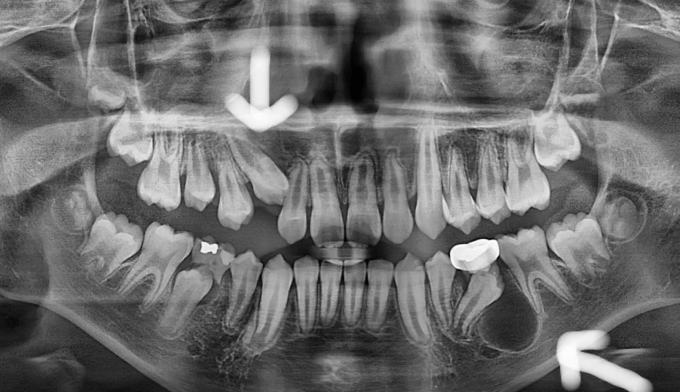

이번 케이스에서는 위쪽 송곳니의 맹출경로이상, 아래쪽 작은어금니는 작은 물혹으로 인해 맹출 경로에 문제가 생겨 교정을 진행한 경우입니다.

물혹을 제거하고 치아 교정장치를 부착하여 간단히 배열하였습니다.